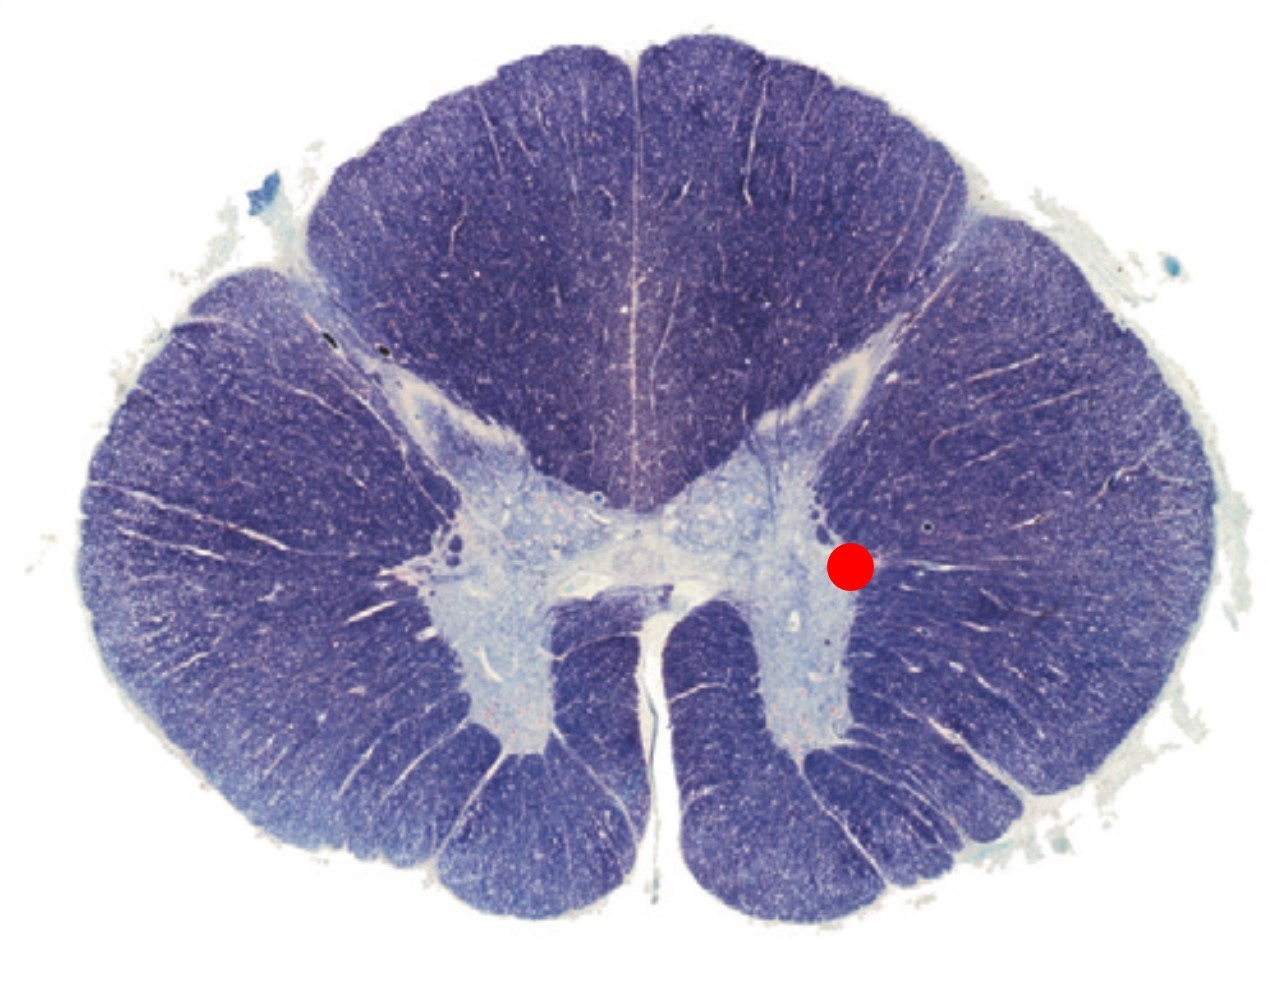

The region of the spinal cord indicated by the red spot:

Contains autonomic neurons

Contains somatic motor neurons

Is present at all levels of the spinal cord

Is the substantia gelatinosa

A